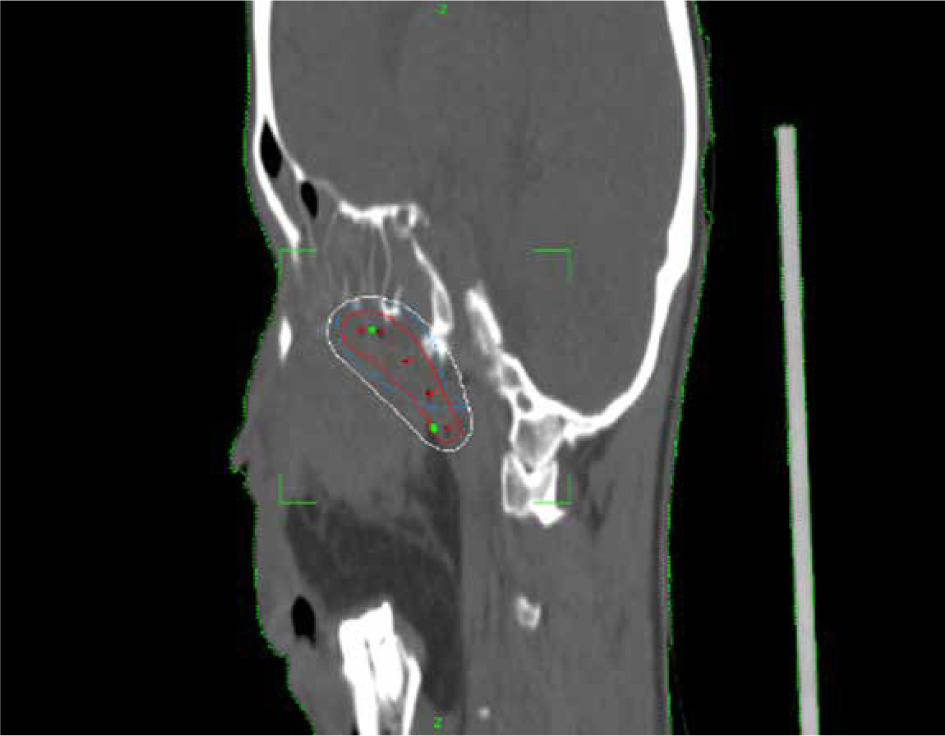

Planning CT was performed on Philips Medical System Cleveland with 3 mm slice thickness encompassing tumor bed, implanted catheters, and a 5 cm cranio-caudal margin. Target volume was considered gross residual tumor, based on the clinician’s assessment, aided in location by bony landmarks, such as pterygomaxillary fissure, temporal process of the zygomatic bone, greater wing of the sphenoid, occipital condyle, and the lateral nasal wall on the opposite side. High-risk clinical target volume (HR-CTV) was generated from the residual volume with a 3 mm margin, and edited based on patterns of spread. The American Brachytherapy Society recommends a CTV based on clinical parameters. In EBRT, a margin of 5 mm is recommended. Due to the proximity of critical neural tissue and in anticipation of high doses close to the implanted catheters, the margin was limited to 3 mm in this case.

A dose of 27.2 Gy in 8 fractions, corresponding to 3.4 Gy per fraction was prescribed to HR-CTV. Sagi-Nova brachytherapy planning system was applied to generate the plan, and dose distribution was optimized by forward planning altering geographical dwell positions if required to ensure adequate coverage of HR-CTV (Figures 2 and 3), while maintaining organs at risk (OARs) constraints to the eye, optic nerve, and chiasma. CT simulation was repeated daily for catheter displacement or positional changes. Images were satisfactory throughout the treatment and no changes were made. The sagittal and axial views of the plan are shown in Figures 2 and 3.